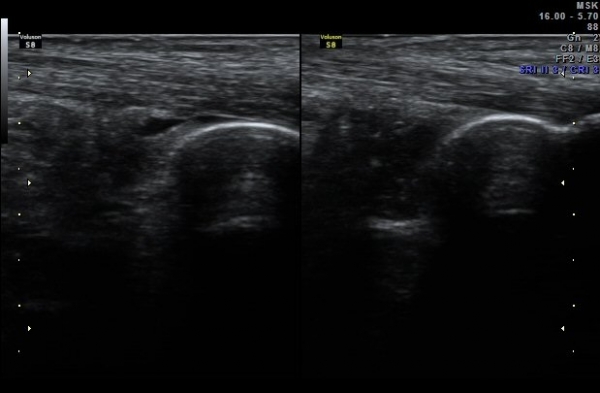

ÃÊÀ½ÆÄ °Ë»ç ÀÌų·¹½º ÈûÁÙ Á¾´Ü¸é°Ë»ç¿¡¼ ¾ÆÅ³·¹½º ÈûÁÙ ½ÉºÎ, Á¾°ñ»À ±ÙÀ§ºÎ¿¡ Ȱ¾×¸· Áõ½Ä°ú

¼ö¾×Àú·ù°¡ °üÂûµÇ°í(±×¸² 1) °ÇÃø°ú ºñ±³Çϸé Â÷À̰¡ ¶Ñ·È´Ù´Ù(±×¸² 2).